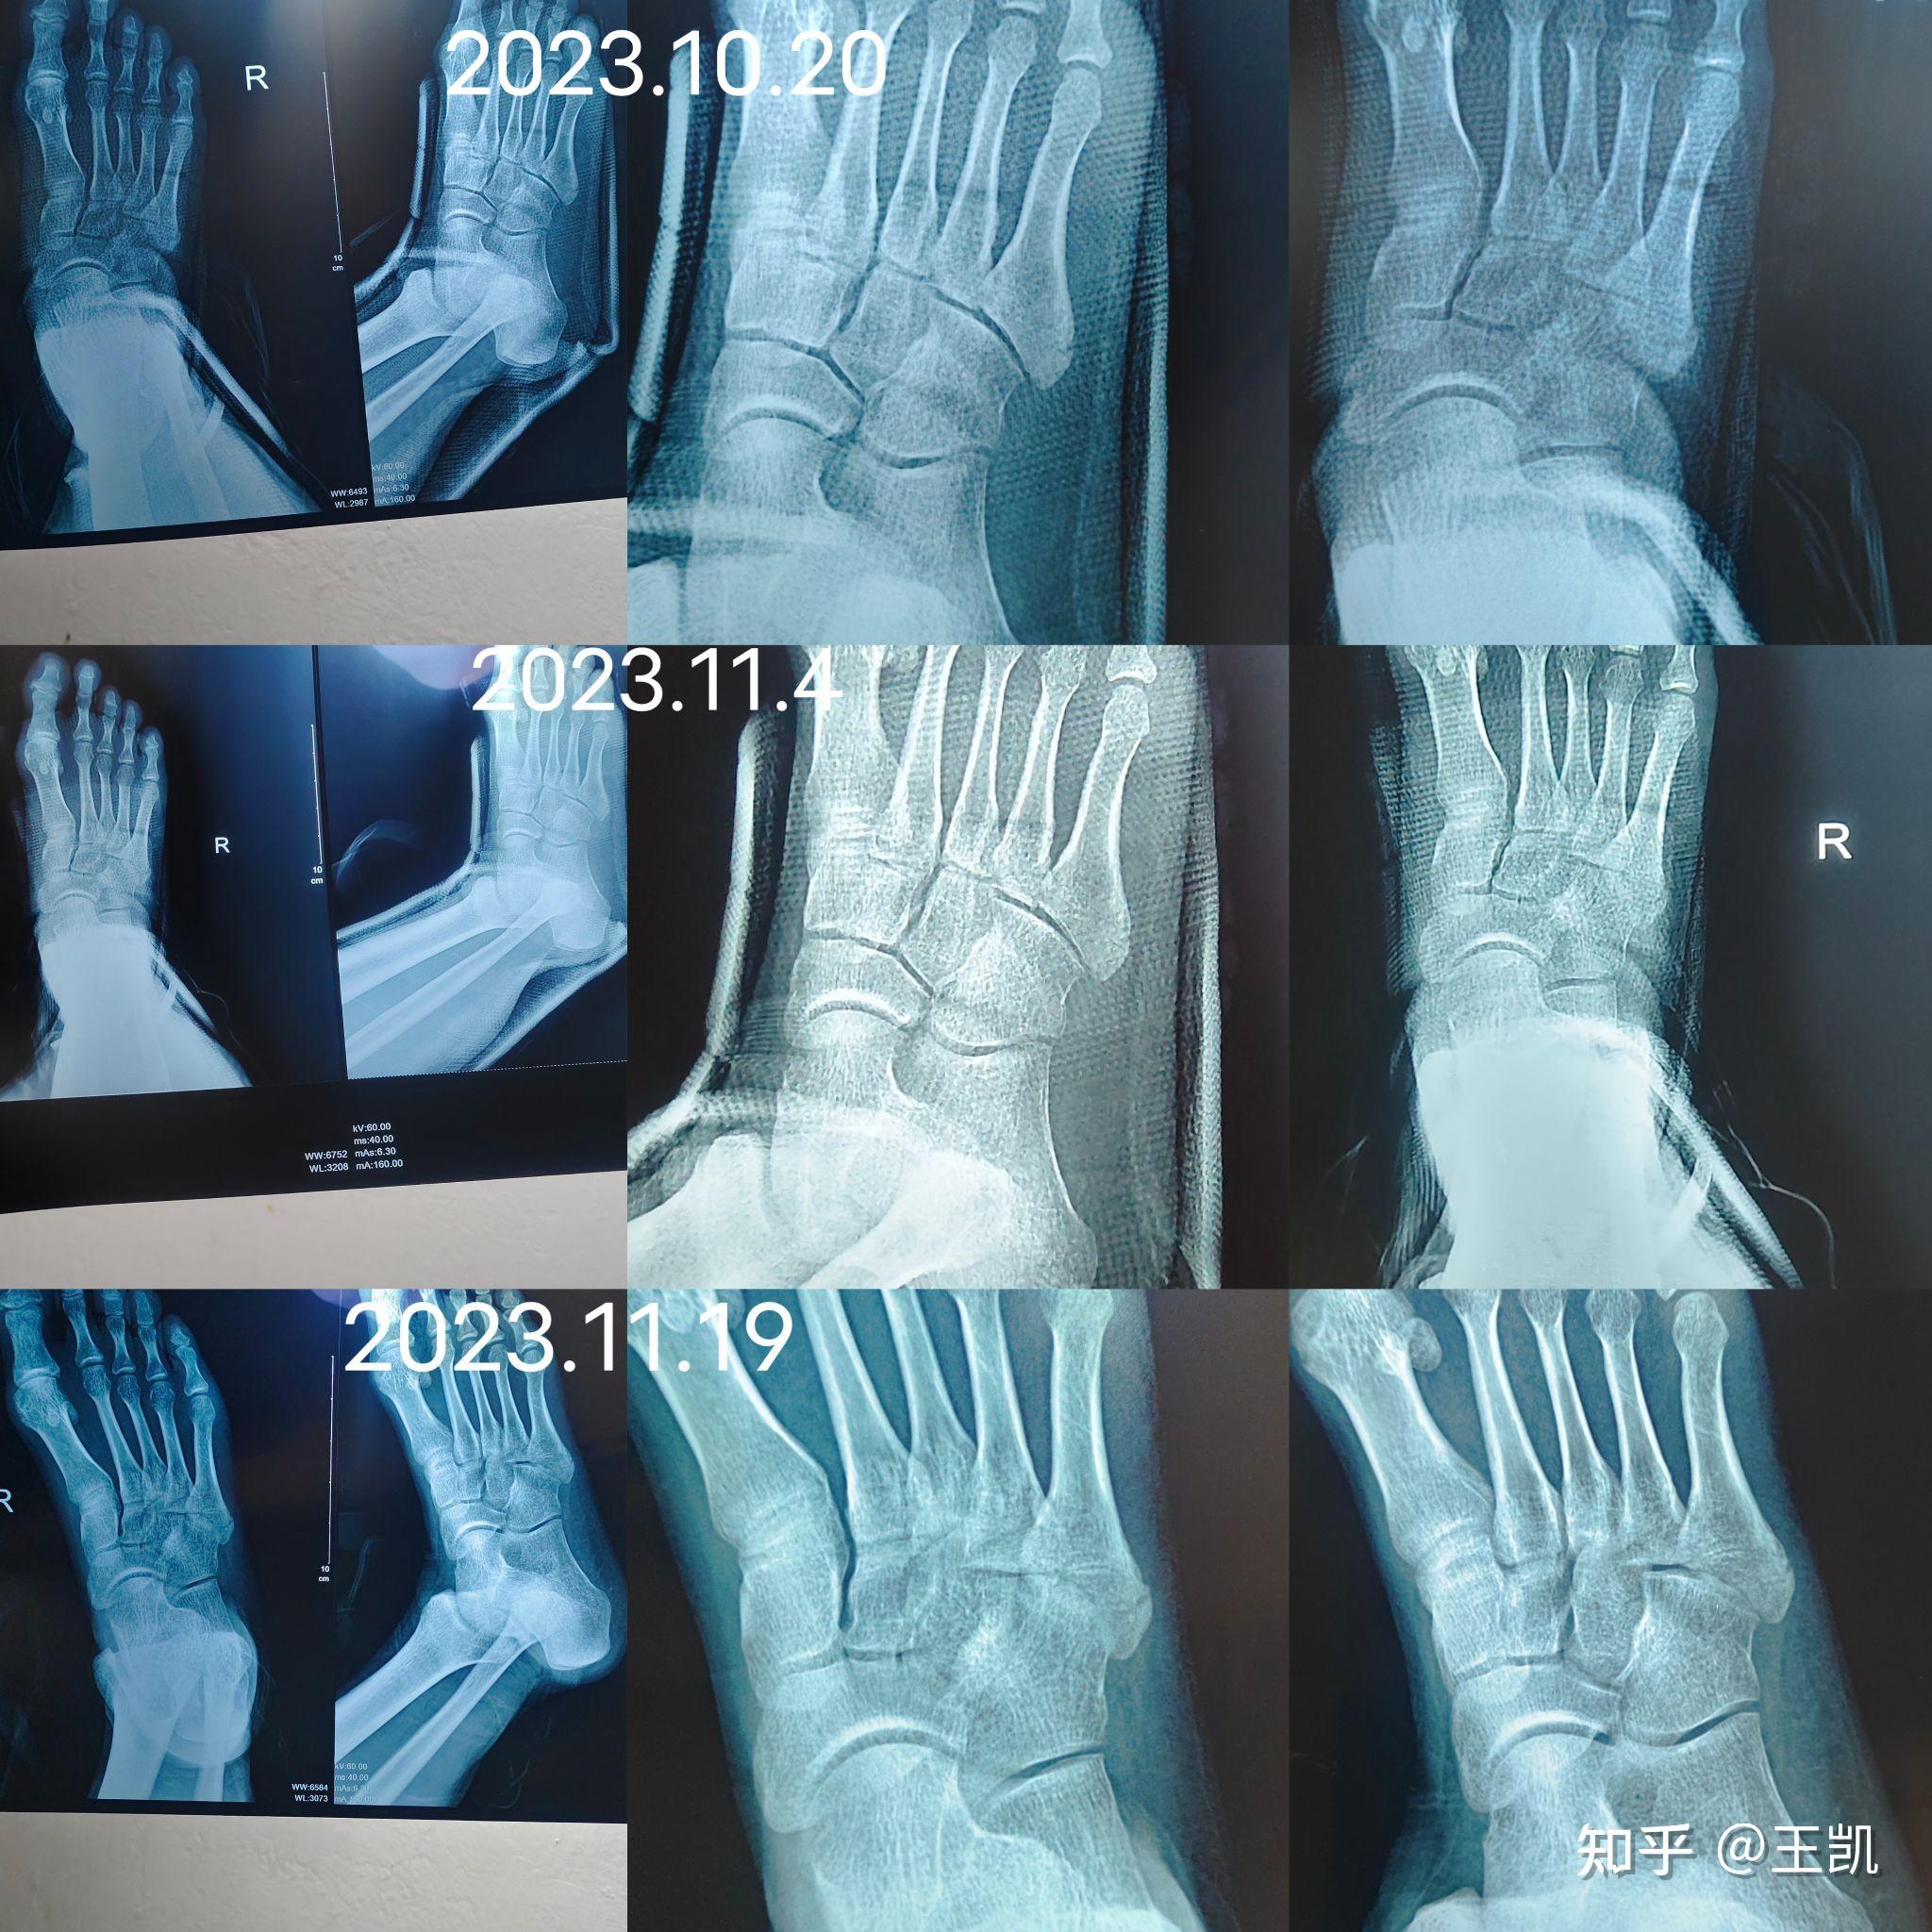

病情分析跖骨骨折,一般是由扭伤车压伤重物打击足部造成的,少数是由于长途行走引起的跖骨颈疲劳性骨折基底部骨折最多,干部次之,颈部最少以横形有些多,斜形有些少受伤以后肿胀,疼疼,皮下出血,影响走路,拍x片子确诊跖骨骨折复位以后用中药接骨药外敷治疗,治疗以后适当固定就可以不。

从提供的右脚照片来看,初步判断可能存在第一近节趾骨骨折的情况,但具体还需结合个人症状和进一步医学检查来确定疑似骨折观察结果片子上似乎显示第一近节趾骨有骨折的迹象,但由于照片清晰度有限,这一判断并不十分确定进一步确认建议前往医院进行X光或CT等影像学检查,以更准确地判断是否存在骨折。

如骨折未愈合前负重,骨折再移位局部会肿胀疼痛加重,皮肤颜色正常,皮肤温度稍高,有明显压疼X线片显示较原骨折间隙宽治疗石膏托固定制动,待骨折愈合即可可配合口服接骨续筋药物不可滥用抗生素。